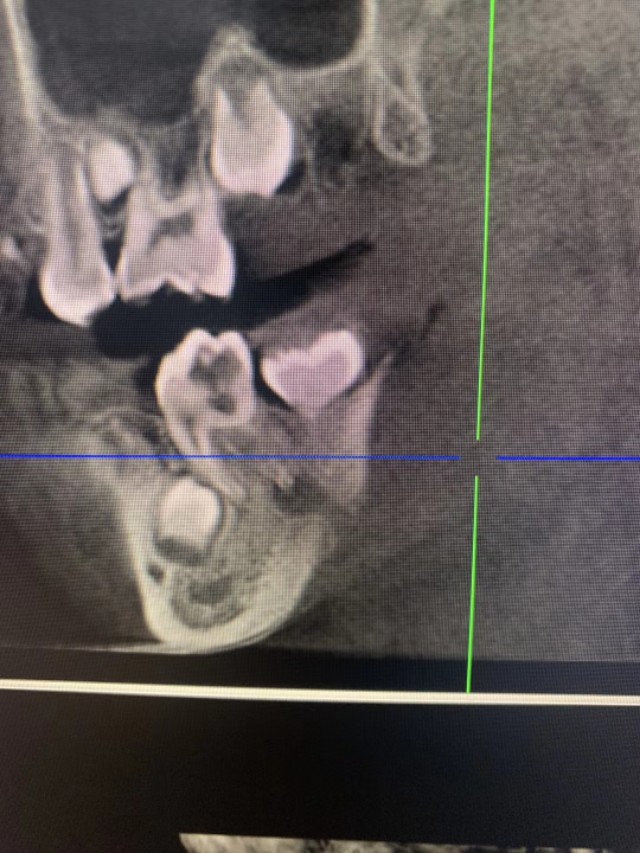

患儿,男性儿童,半年前出现右侧颌面反复流脓,家属半年碾转就诊于数家医院的耳鼻咽喉科和口腔科,多次切开排脓不愈,最后一次在我老师所在科室行全麻瘘管局部清扫手术,自认为手术彻底,谁知10余天后就复发,百思不得其解,复诊时口腔检查,终于发现右下一牙轻微叩痛,(患儿未诉牙自发症状),嘱其再返口腔科就诊,拔除患牙,右颌下瘘管随之而愈,虽然患儿最终得以痊愈,但是过程曲折受尽折磨,患儿的主刀医生已经是头颈外科的顶级专家,依然难免会有差错的时候,行医之路,如履薄冰,特以同道分享!

2、术中未见瘘管,均为肉芽,术后病理亦未报瘘管,只报炎症,未起疑心

3、术中并未见下颌骨皮质受损(是否舌侧可能),排除了牙源性可能